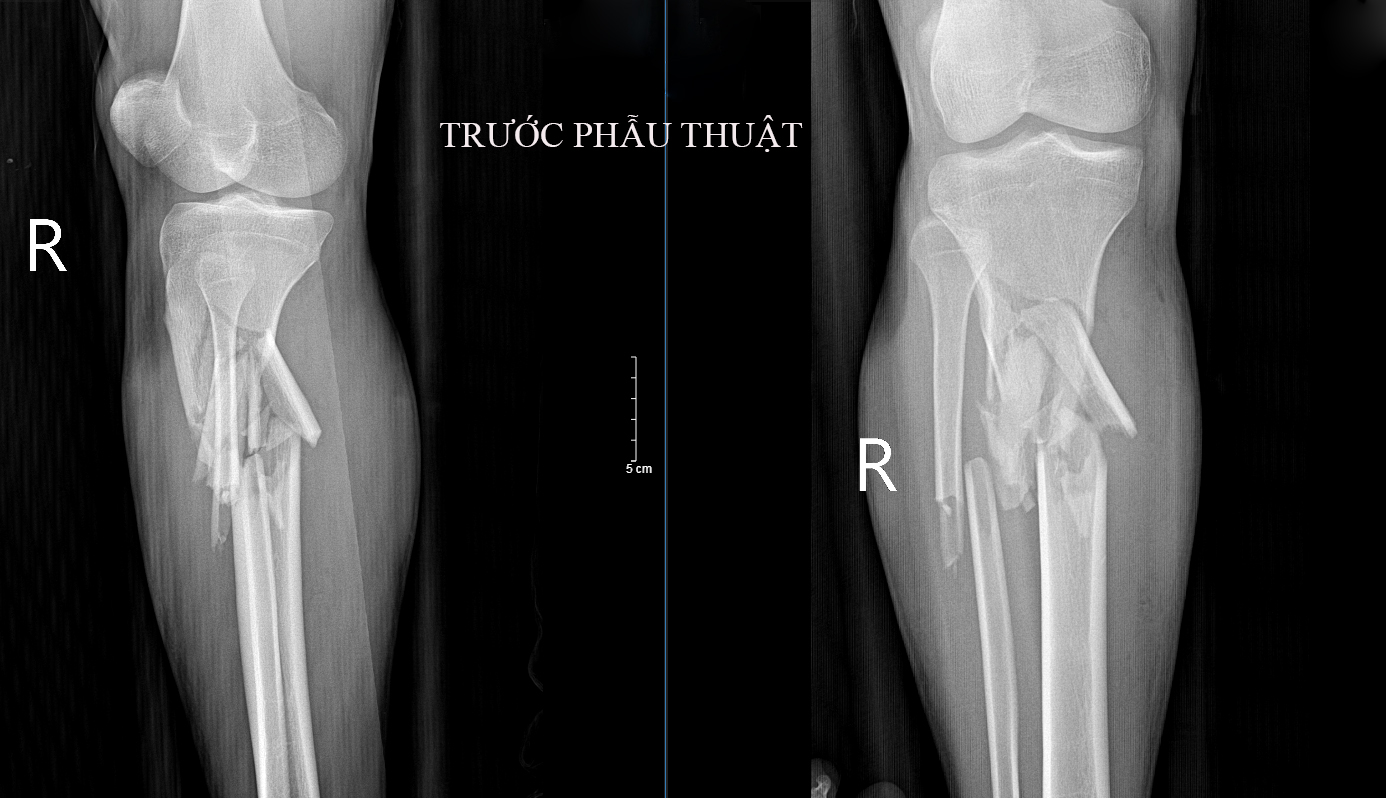

Ngày 16/12, Trung tâm Y tế huyện Chiêm Hóa tiếp nhận một bệnh nhân nam bị tai nạn xe máy. Qua thăm khám, bệnh nhân bị mất vận động cẳng chân hai bên, chân phải xây xát nhiều, biến dạng vùng cẳng chân, ấn đau chói, mạch chày trước, sau khó xác định. Tại cẳng chân trái ấn đau chói 1/3 giữa, mạch chày trước sau rõ. Bệnh nhân được chỉ định làm các xét nghiệm cận lâm sàng, chup X-quang… Kết quả Chụp Xquang: Gẫy,vỡ phức tạp 1/3 trên hai xương cẳng chân phải. Xương gẫy di lệch. Bệnh nhân đã được bó bột nhưng không có kết quả. Chụp XQ sau bó bột Kết luận: Hình ảnh mảnh xương vỡ chưa đúng vị trí; Xương mác lệch trục.

Hình ảnh XQ trước phẫu thuật